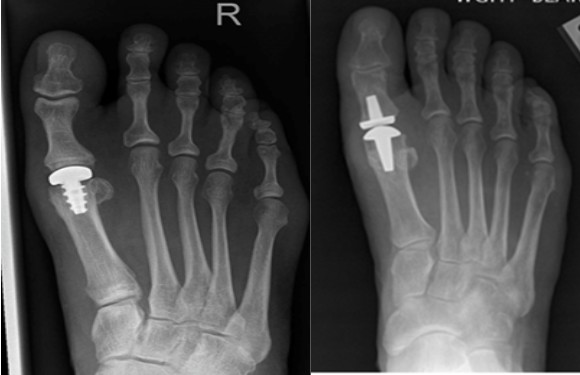

- Костные элементы фиксируются компрессионными винтами из титана. Эти винты обычно не вызывают дискомфорта у пациента, поэтому их не удаляют. Однако, если через три месяца после операции возникает необходимость, их можно извлечь.

- Фрагменты сустава надежно фиксируются с помощью винтов.

Эти действия восстанавливают структуру сустава, что приводит к полному исчезновению симптомов. Винты после операции не удаляются.

| Артродез первого плюснефалангового сустава | Фиксация сустава в правильном положении с помощью винтов или пластин. | Тяжелая деформация, выраженный артроз, неэффективность других методов лечения. Противопоказано при активном воспалении, плохом состоянии мягких тканей. |

| Имплантация эндопротеза первого плюснефалангового сустава | Замена поврежденного сустава на искусственный. | Тяжелый артроз, неэффективность других методов лечения. Противопоказано при инфекции, плохом состоянии мягких тканей, активном воспалении. |